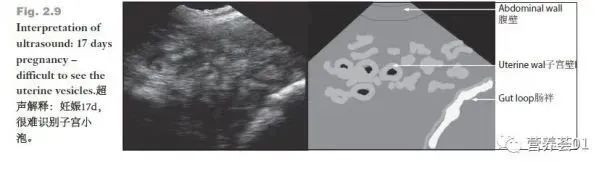

妊娠17天,很难识别孕囊(子宫小泡)

现场很少会将已经怀孕的母猪误诊为空怀。但一些空怀母猪却可能会被误诊为已妊娠。常见的误诊来源是将黑点误认为是胚囊从而判断母猪已经受孕,或者将子宫内液体形成的多个小黑点认为是早期妊娠或疑似妊娠。